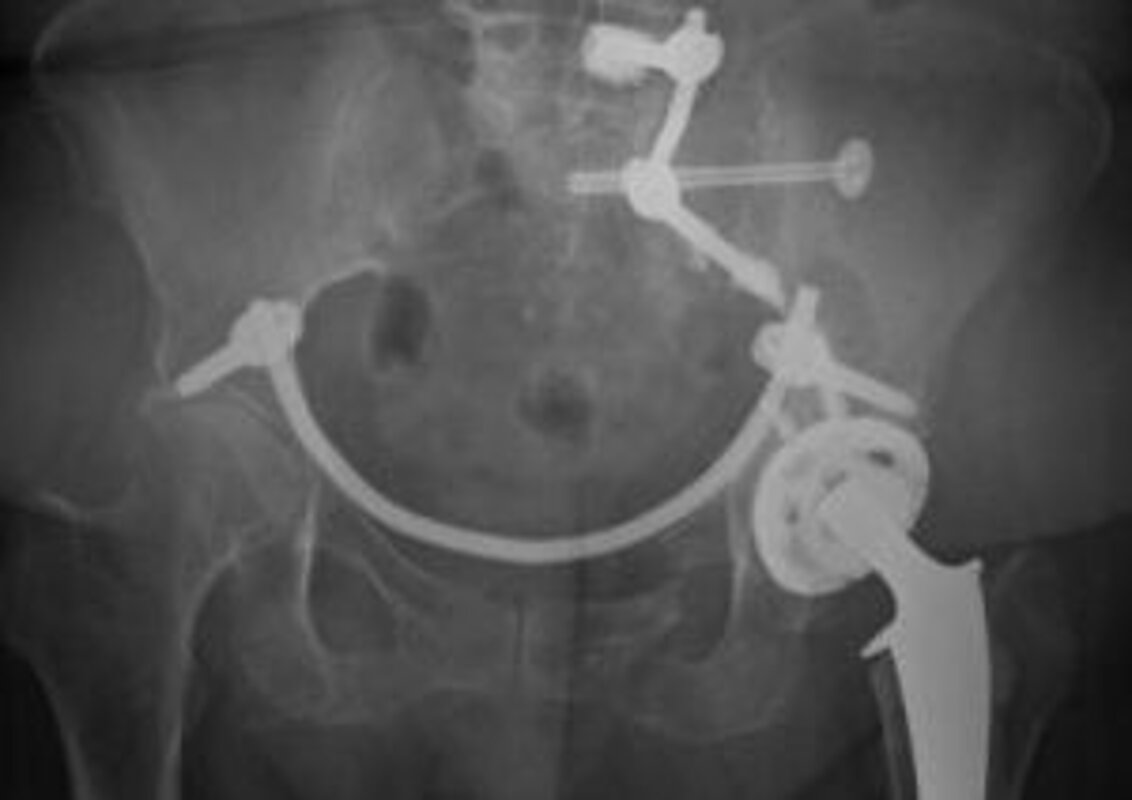

Auch bei der operativen Frakturversorgung gibt es aufgrund von Morbidität und Osteoporose eine Vielzahl von Herausforderungen. Darunter fallen unter anderem die Frakturen des Beckenrings, dessen Behandlung nach wie vor kontrovers diskutiert wird.